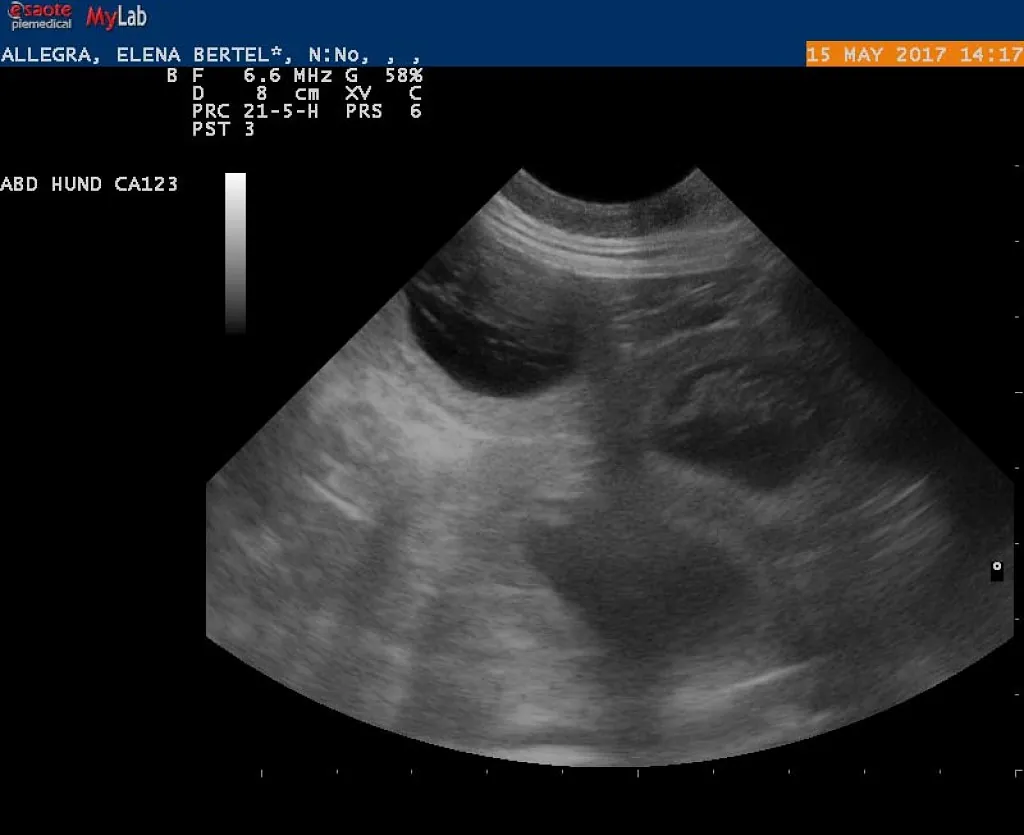

15.05.2017

Alice er drægtig!

e-kuld, 2017, sommer, kennel basta dog, schnauzere, schnauzerhvalpe, schnauzeropdræt, mellemschnauzer, alenzo, alice, hvalpe, købe schnauzer

Dejlig, dejlig nyhed!!!

Alice (Allegra)  er drægtig!

Scanning i dag har nemlig bekræftet den dejlige nyhed!

Hvor mange hvalpe er der inde? Tja, en del af dem kan du se på de billeder fra scanning :)

Nu krydser vi fingre for at alt går godt og vi får dejlige hvalpe efter de smukke og dygtige forældre!

P.S. Scaninngsbillederne ved klik på dem vil kunne ses i større størelse!